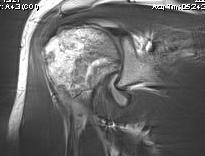

MRI

Sensitivity and specificity approach 100%

T1

- areas low signal intensity on T1 representing edema

- areas of high signal intensity thought to represent blood flow

T2

"Double line sign"

- highly specific for AVN

- inner bright line representing granulation tissue

- outer dark line representing sclerotic bone

Stage I - pre-xray change / diagnosed on MRI